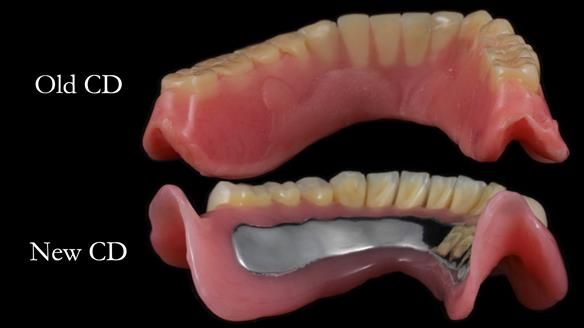

The detailed clinical situation and treatment process are outlined below, with clinical work provided by me and technical work by Rowan Garstang. The treatment spanned 12 months, involving removing 5 upper anterior teeth, adding to an existing upper RPD, followed by creating and fitting metal based complete dentures.